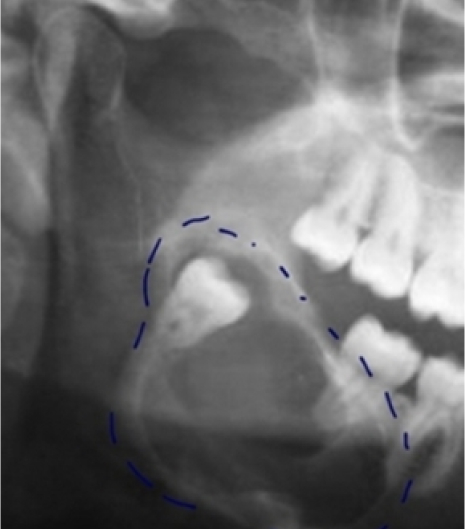

Digitális panoráma röntgen

Modern, alacsony sugárzású röntgenfelvételt készítünk, amellyel pontosan láthatjuk a fogak pozícióját és azt, hogy van-e elegendő hely az állkapocsban a bölcsességfog számára. Amennyiben a röntgen kérdéses vagy kockázatos helyzetet mutat, a rendelőnkben elérhető 3D CT felvétel, hogy minden oldalról megvizsgálhassuk a fogait.

A röntgen és a vizsgálat alapján részletesen átbeszéljük, hogy szükséges-e a bölcsességfog eltávolítása, vagy csak folyamatos megfigyelést igényel. Amennyiben az eltávolítás javasolt, úgy megkeressük a műtét szempontjából legideálisabb pillanatot. Minden esetben részletes tájékoztatást kap a fog eltávolításának előnyeiről, esetleges kockázatairól.